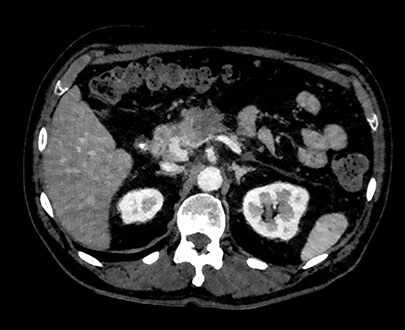

MonoE zakresie 200keV

Suwak wyboru energii 200keV

Badanie MonoE pozwala uzyskać zsyntetyzowane obrazy monoenergetyczne przy wstępnie zdefiniowanych wartościach w zakresie od 40 keV do 200 keV. Wygląd obrazów zmienia się wraz ze zmianą wartości keV, nawet jeśli ustawienia okna/poziomu są takie same. Przykładowo przy niższych wartościach keV jod może wydawać się jaśniejszy, natomiast wyższe wartości keV pozwalają ograniczyć artefakty pochodzące od metalowych implantów.